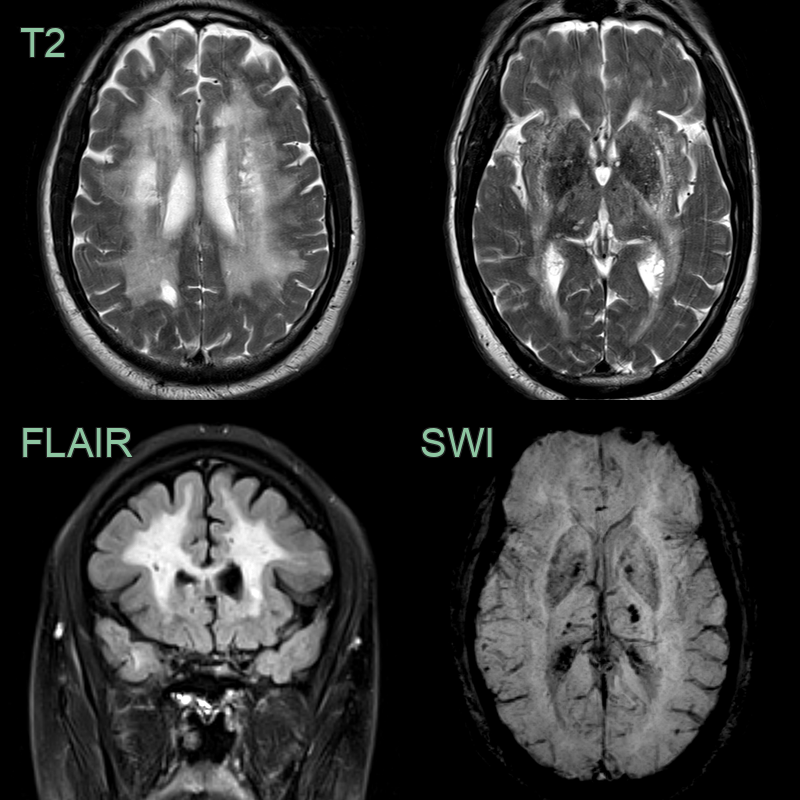

• A 55-year-old patient with no cardiovascular risk factors presented with recurrent headache.

• MRI showed a confluent leukoencephalopathy, involving the external capsules and anterior temporal lobes, and lacunar infarcts.

• There were deep and lobar microhemorrhages.